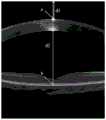

图2为本发明待测眼角膜和视网膜的OCT二维层析成像结果示意图。FIG. 2 is a schematic diagram showing the results of OCT two-dimensional tomography of the cornea and retina of the eye to be tested according to the present invention.

所述S6中,将待测眼角膜的OCT二维层析成像结果和视网膜的OCT二维层析成像结果合并为待测眼的OCT二维层析成像结果,将待测眼的OCT二维层析成像结果的上边界作为零光程差位置,利用边界识别方法对待测眼的OCT二维层析成像结果进行图像处理后获得待测眼的角膜前表面和视网膜色素上皮细胞层。In the S6, the OCT two-dimensional tomography results of the cornea to be measured and the OCT two-dimensional tomography results of the retina are combined into the OCT two-dimensional tomography results of the eye to be measured, and the OCT two-dimensional tomography results of the eye to be measured are combined. The upper boundary of the tomography result is taken as the zero optical path difference position, and the front corneal surface and retinal pigment epithelium cell layer of the eye to be measured are obtained after image processing of the OCT two-dimensional tomography result of the eye to be measured by using the boundary recognition method.

所述S6中,记待测眼角膜前表面的顶点a至零光程差位置之间的距离为d1,记顶点a与零光程差位置之间的距离的延长线与视网膜色素上皮细胞层的交点为b,交点b与零光程差位置之间的距离为d2,眼后节光程调节装置位移台的位移为d3,则待测眼的眼轴长D满足D=d2–d1+2×d3。In the S6, the distance between the vertex a on the anterior surface of the cornea to be measured and the position of zero optical path difference is d1, and the extension line of the distance between vertex a and the position of zero optical path difference and the retinal pigment epithelial cell layer are recorded. The intersection point is b, the distance between the intersection point b and the zero optical path difference position is d2, and the displacement of the optical path adjustment device displacement stage of the posterior segment of the eye is d3, then the axial length D of the eye to be measured satisfies D=d2–

将待测眼12角膜的OCT二维层析成像结果和视网膜的OCT二维层析成像结果合并为待测眼12的OCT二维层析成像结果,将待测眼12的OCT二维层析成像结果的上边界作为零光程差位置,利用边界识别方法对待测眼12的OCT二维层析成像结果进行图像处理后获得待测眼12的角膜前表面和视网膜色素上皮细胞层,记待测眼12角膜前表面的顶点a至零光程差位置之间的距离为d1,记顶点a与零光程差位置之间的距离的延长线与视网膜色素上皮细胞层的交点为b,交点b与零光程差位置之间的距离为d2,眼后节光程调节装置位移台的位移为d3,则待测眼12的眼轴长D满足D=d2–d1+2×d3。The OCT two-dimensional tomographic imaging result of the cornea of the eye to be tested 12 and the OCT two-dimensional tomographic imaging result of the retina are combined into the OCT two-dimensional tomographic imaging result of the eye to be tested 12, and the OCT two-dimensional tomographic imaging result of the eye to be tested 12 is combined. The upper boundary of the imaging result is taken as the position of zero optical path difference, and the OCT two-dimensional tomography results of the eye to be measured 12 are image-processed by using the boundary recognition method to obtain the anterior corneal surface and the retinal pigment epithelial cell layer of the eye to be measured 12. The distance between the vertex a of the anterior surface of the cornea and the position of zero optical path difference is d1, and the intersection of the extension line of the distance between vertex a and the position of zero optical path difference and the retinal pigment epithelium layer is b, and the intersection point The distance between b and the position of zero optical path difference is d2, and the displacement stage of the posterior segment optical path adjustment device is d3, then the axial length D of the